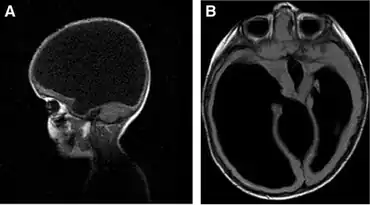

Hydranencephaly

Hydranencephaly is a condition in which the cerebral hemispheres are missing and instead filled with sacs of cerebrospinal fluid. People are born with hydranencephaly, but most of the time, the symptoms appear in a later stage. Newborns with hydrancephaly can swallow, cry, sleep and their head is in proportion to their body. However, after a few weeks, the infants develop increased muscle tone and irritability. After a few months, the brain start to fill with cerebrospinal fluid (hydrocephalus). This has several consequences. Infants start to develop problems with seeing, hearing, growing, and learning. The missing parts of the brain and the amount of cerebrospinal fluid can also lead to seizures, spasm, problems with regulating their body temperature, and breathing and digestion problems. Besides problems in the brain, hydranencephaly can also be seen on the outside of the body. Hydrocephalus leads to more cerebrospinal fluid in the brain, which can result in an enlarged head.[9][10][11]

The cause of hydranencephaly is not clear. Hydranencephaly is a result of an injury of the nervous system or an abnormal development of the nervous system. The neural tube closes in the 6th week of the pregnancy,[12] so hydranencephaly develops during these weeks of the pregnancy. The cause of these injuries/development is not clear.